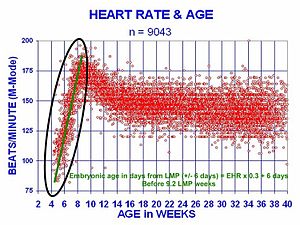

The human embryonic heart begins beating around 21 days after conception, or five weeks after the last normal menstrual period (LMP), which is the date normally used to date pregnancy. It is unknown how blood in the human embryo circulates for the first 21 days in the absence of a functioning heart. The human heart begins beating at a rate near the mother’s, about 75-80 beats per minute (BPM). The embryonic heart rate (EHR) then accelerates linearly for the first month of beating, peaking at 165-185 BPM during the early 7th week, (early 9th week after the LMP). This acceleration is approximately 3.3 BPM per day, or about 10 BPM every three days, an increase of 100 BPM in the first month.

After peaking at about 9.2 weeks after the LMP, it decelerates to about 152 BPM (+/-25 BPM) during the 15th week after the LMP. After the 15th week the deceleration slows reaching an average rate of about 145 (+/-25 BPM) BPM at term. The regression formula which describes this acceleration before the embryo reaches 25 mm in crown-rump length or 9.2 LMP weeks is Age in days = EHR(0.3)+6

There is no difference in male and female heart rates before birth.